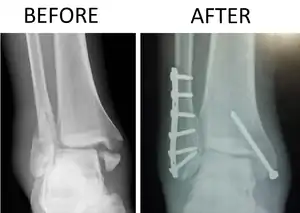

| X-ray of trimalleolar fracture repair before and after ORIF surgery | |

Surgical repair using open reduction and internal fixation is generally required, and because there is no lateral restraint of the foot, the ankle cannot bear any weight while the bone knits. This typically takes six weeks in an otherwise healthy person, but can take as much as twelve weeks. Non-surgical treatment may sometimes be considered in cases where the patient has significant health problems or where the risk of surgery may be too great.[1]